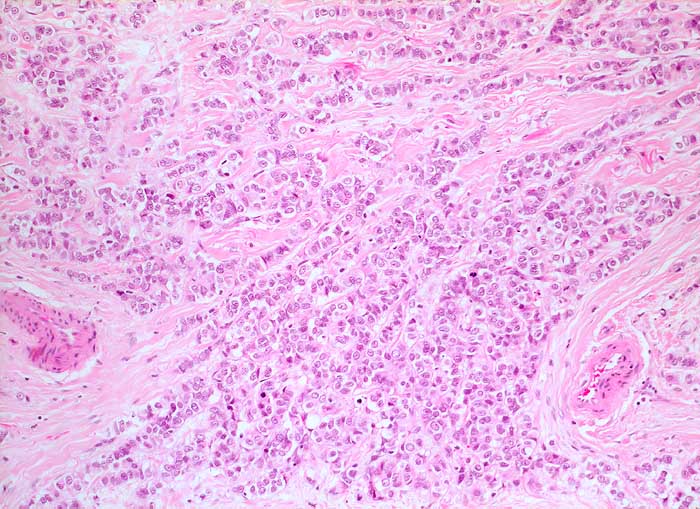

PathoPic ID 5905 - invasiv lobuläres Mammakarzinom

invasiv lobuläres Mammakarzinom

Die monomorphen Tumorzellen sind in Einerreihen angeordnet. Zwischen den Zellreihen desmoplastisches Stroma.

Metastasierendes Mammakarzinom

Histologie

200